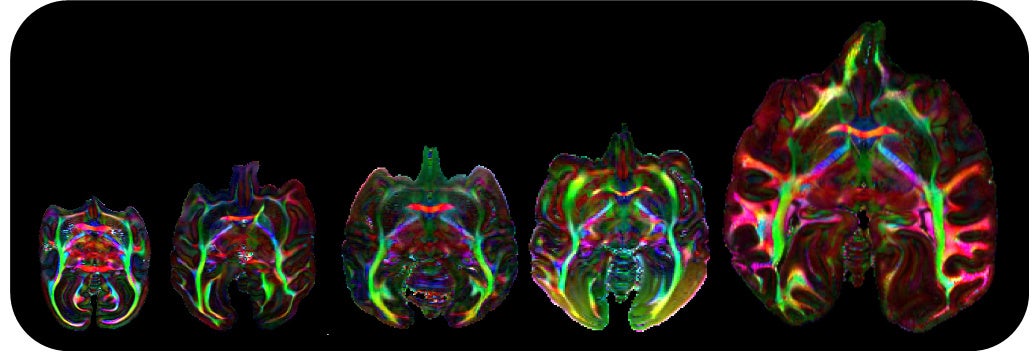

革新脳および戦略的国際脳科学研究推進プログラム(以下、国際脳)(注2)との連携体制をもつ本研究グループは、世界最大級の霊長類脳標本コレクション (注3)を対象に、超高磁場MRI装置(注4)を用いて、脳標本を切り出すことなく神経線維の連絡性を可視化した拡散テンソル画像(diffusion tensor imaging; DTI画像)(注5)を撮像する顕微鏡的MRI技術を開発し、体重100gほどのマーモセットから体重38㎏のチンパンジーにまでわたる霊長類種の神経回路の多様性を全脳レベルで描出することに成功しました (図1)。本脳画像リポジトリは、今回の発表論文で第2フェーズへと入り、さらに、多様な霊長類の脳情報を包括的に提供することで、データ駆動型科学を通したヒト脳の特徴や精神・神経疾患の解明に貢献しています。本論文はこれまでの活動が国際的にも認められ、招待論文として「Neuroimage」のオンライン版に2023年4月7日に掲載されました。

図1 霊長類「全脳」神経回路の多様性

左から順に、ボリビアリスザル、ノドジロオマキザル、クロザル、チベットモンキー、チンパンジー